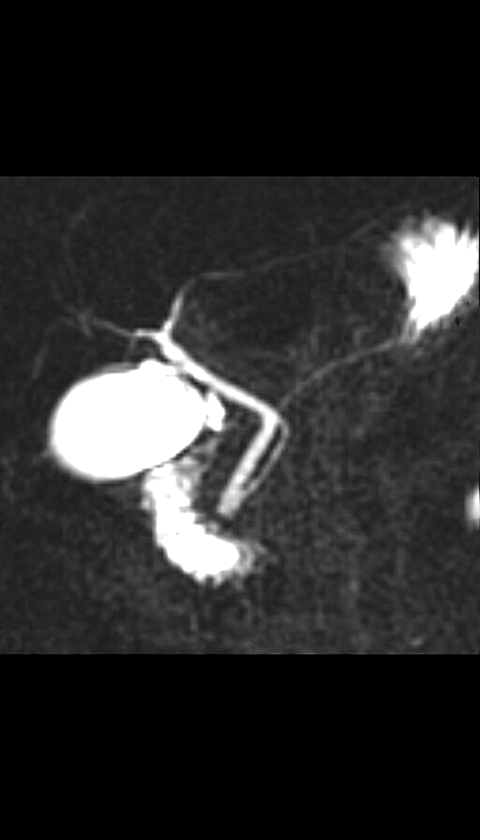

MR cholangiopancreatogram (coronal)